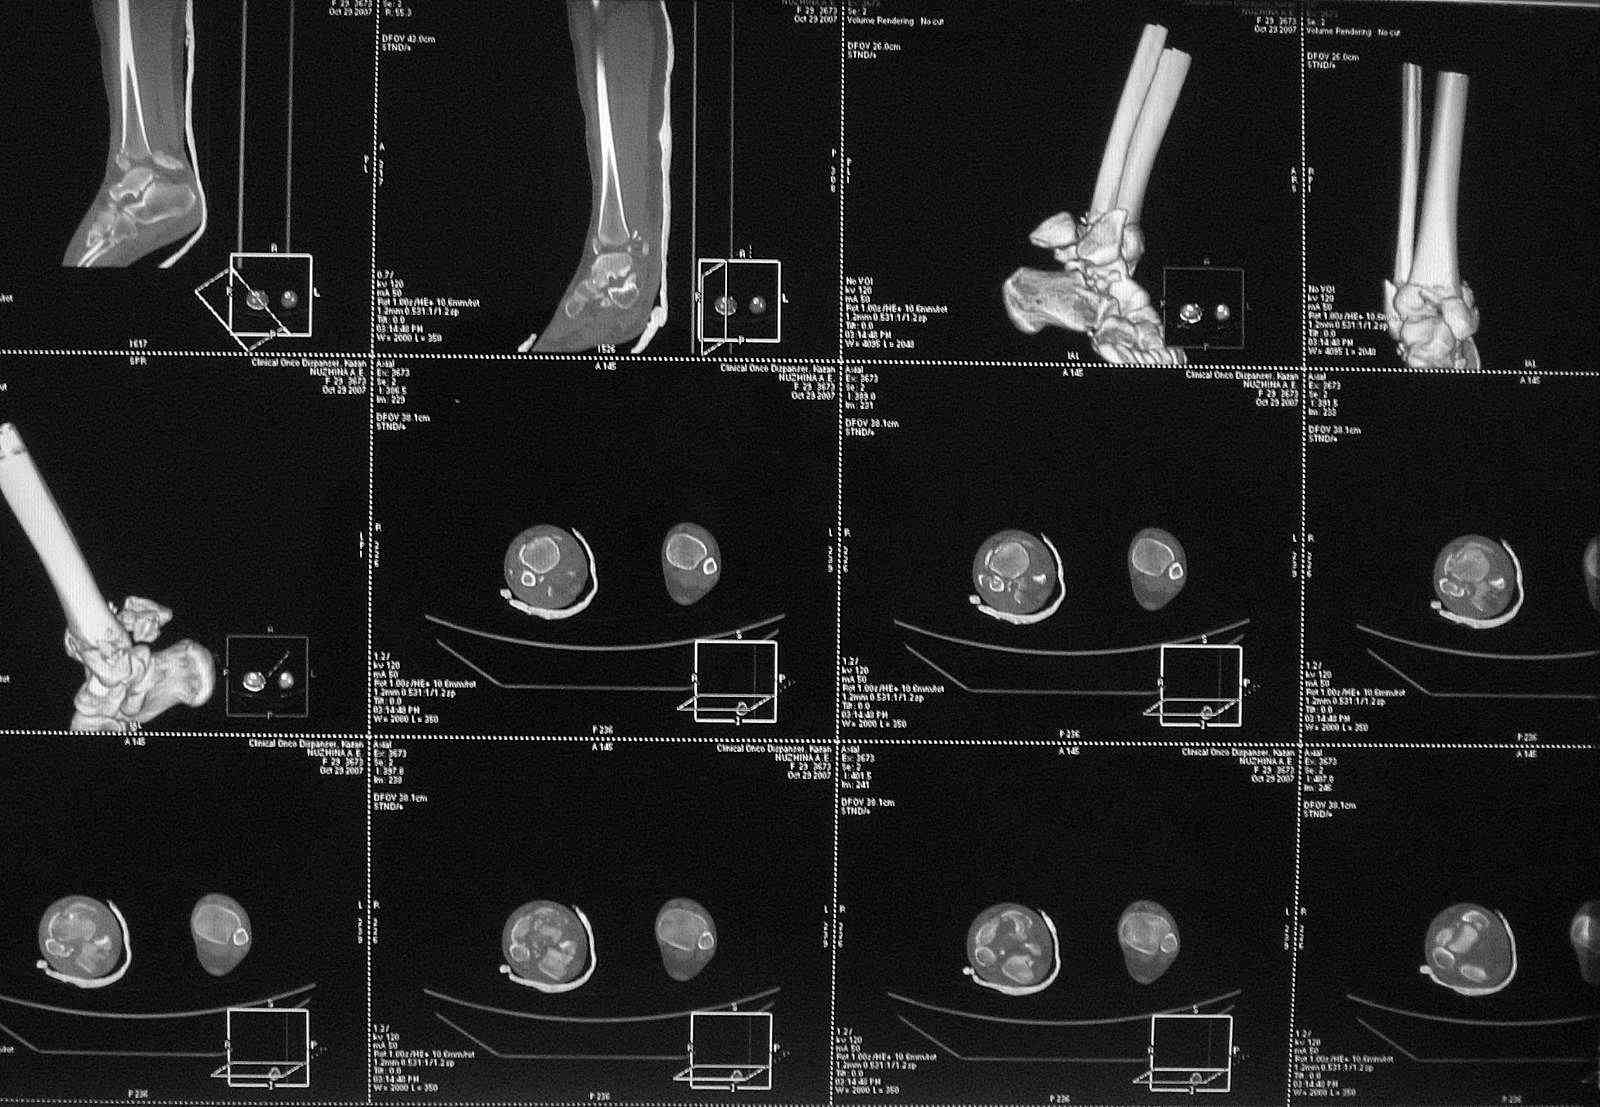

[Ortho] Перелом пилона

Добавлены КТ снимки. Прошу прощения за качество.